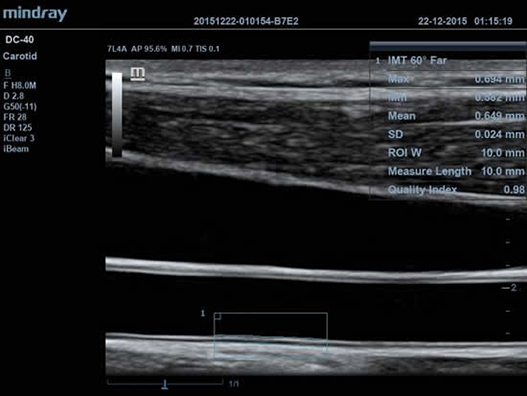

• Функция Auto IMT автоматически измеряет толщину комплекса интима-медиа.

• Auto IMT Package – измерения и анализ толщины комплекса интимамедии (КИМ) сонной артерии;

• Мультичастотный линейный датчик Mindray L14-6